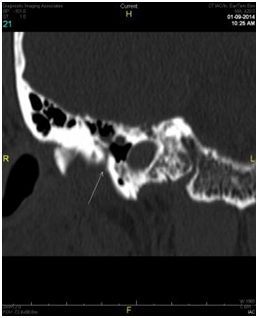

Two months later, a third operative procedure was performed for excision of a further recurrence of the granuloma in the anterior superior portion of the ear canal. Following this third procedure, the idea of a herniation through a bony defect in the anterior canal wall was finally considered. A second CAT scan of the temporal bones was performed. This scan revealed a soft tissue density closely associated with the tympanic membrane in the external auditory canal on the right just anterior to it and what appeared to be a small defect or thinning of the anterior canal wall just posterior to the temporomandibular joint. Axial and coronal views of the defect in the anterior wall are shown in Figures 2 (A & B) and demonstrate conclusively the presence of a patent foramen of Huschke. Further examination revealed motion of the lesion with mastication. The patient’s facial asymmetry was determined to be a consequence of mandibular asymmetry.

Figure 2(A) Axial image at the level of the condylar head of the mandible at the Tmj joint. The arrow depicts a small defect in the anterior wall of the external auditory canal with soft tissue density that is contigious with the Tmj joint. This is closely approximated to the soft tissue density that abuts the tympanic membrane.